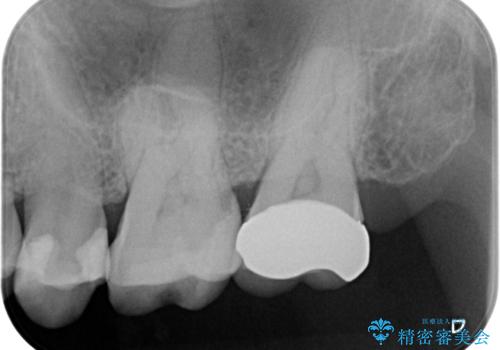

- 口の中に見える銀歯を、金属アレルギーの対策と審美性の向上のため全て除去したい!と希望され来院されました。

銀歯を丁寧に除去したのち、精度の良いセラミックインレー、セラミッククラウンで修復・補綴処置を行っていきます。

- 62.7万円(ジルコニアクラウン×3・仮歯×3・セラミックインレー×3)費用は治療当時の料金となります